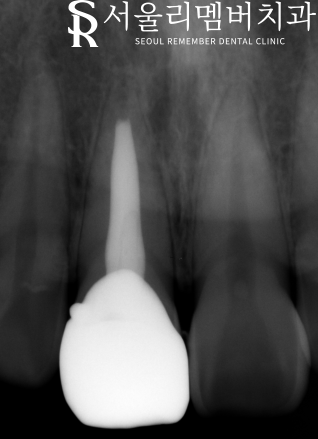

신경치료 완료 후 크라운 후 찍은 Standard x-ray 입니다.

뿌리 끝까지 수복재료가 잘 들어가 있는 모습입니다.

크라운 위쪽으로 자세히 보시면 기둥(post)이 보입니다.

안정적으로 기둥을 세우고

크라운 치료까지 완료 하였습니다.

크라운 쪽에 볼록 튀어 나와있는 것은 훅이라고

저희가 크라운을 끼고 뺄때 잡는 손잡이입니다.